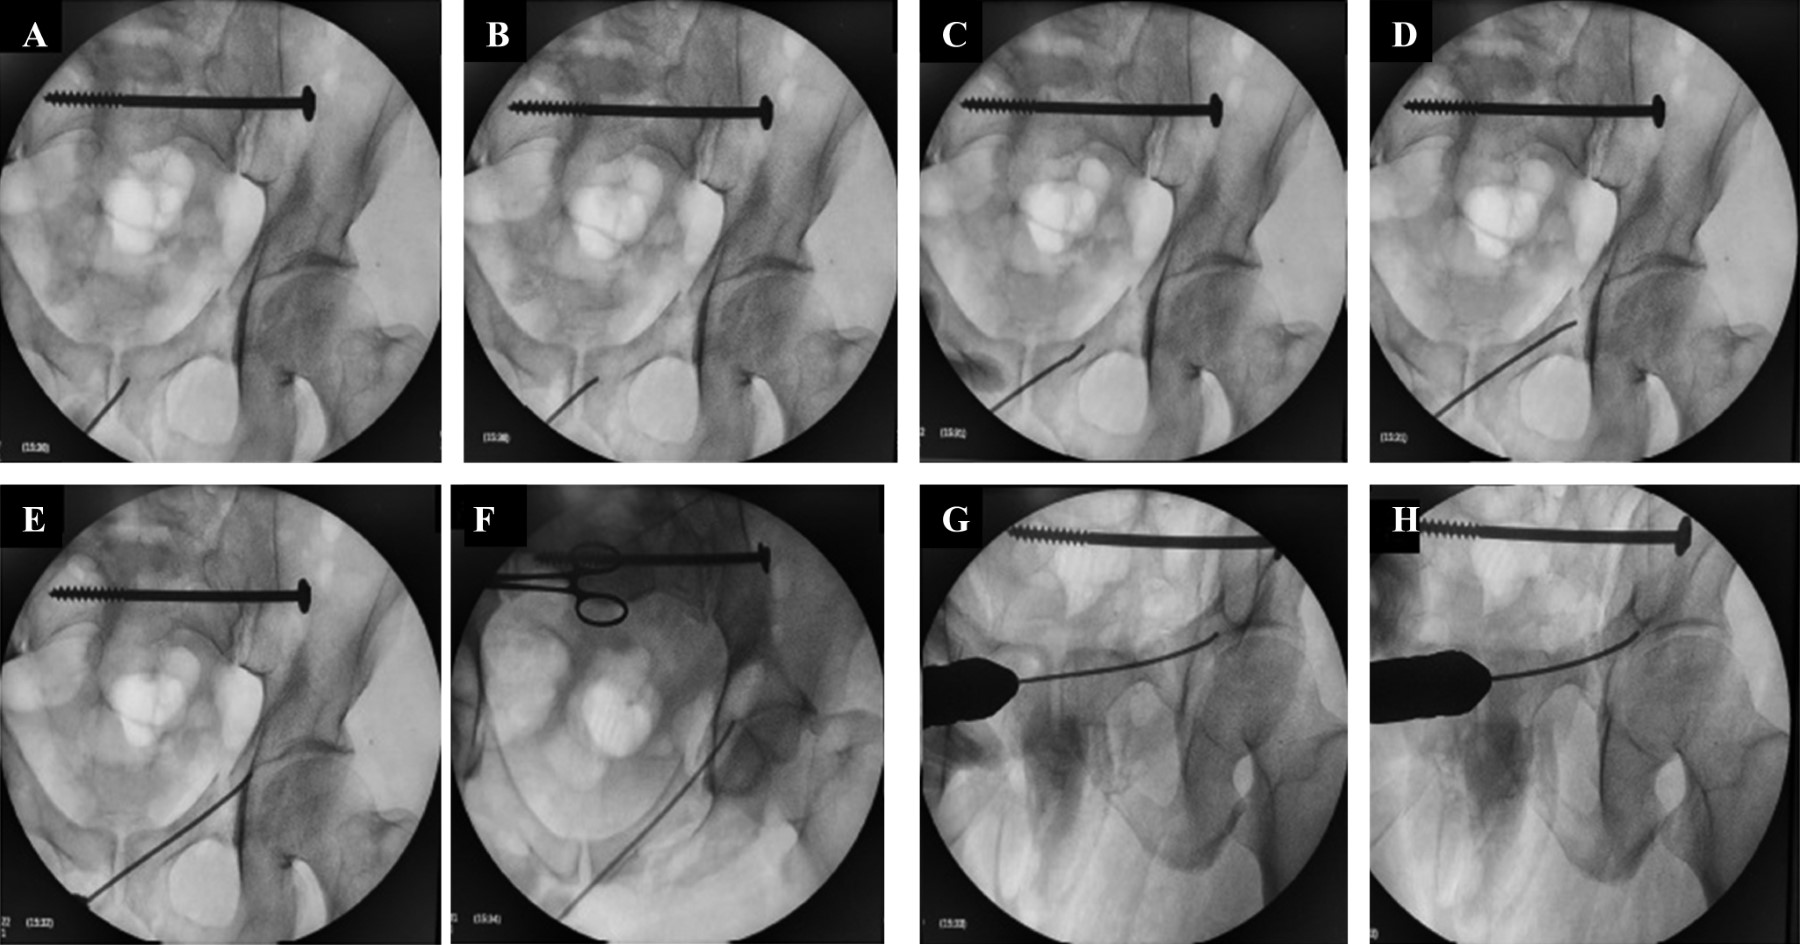

Figura 4